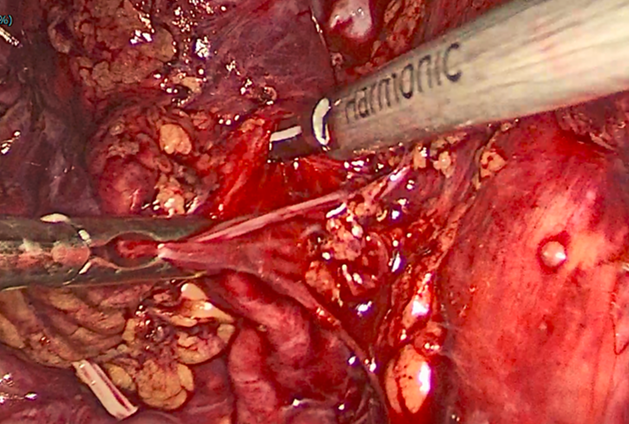

游离肾静脉,发现因长期压迫,肾实质萎缩影响,肾静脉也已萎缩

仔细游离将萎缩的动脉离断,多重夹闭防止出血